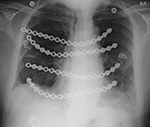

| PA Chest radiograph (A) demonstrates a sternal cage. Whole body Tc99m MDP images (B) demonstrate focal radiotracer activity in ribs bilaterally on the anterior view representing the sites of sternal cage fixation with bony reaction. |